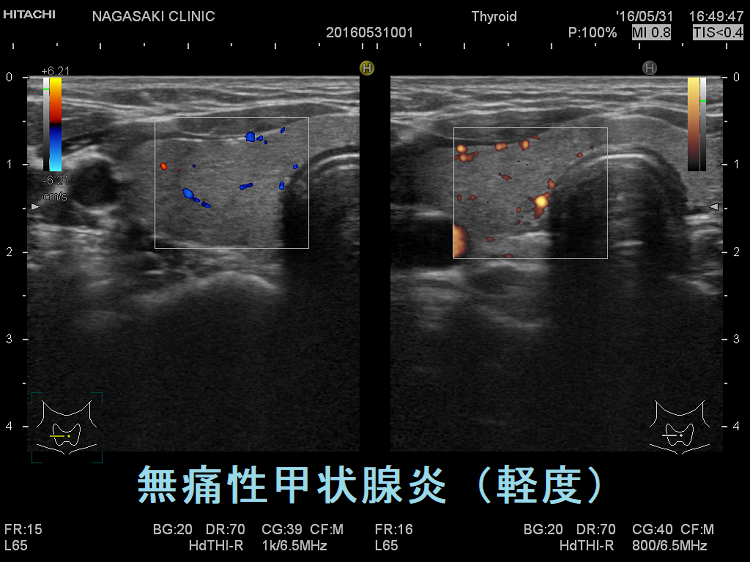

vascular index(血流指数)が増加した無痛性甲状腺炎

vascular index(血流指数)が増加した急性期の無痛性甲状腺炎の下甲状腺動脈の収縮期最大血流速度(ITA-PSV);ITA-PSVは低下しています。